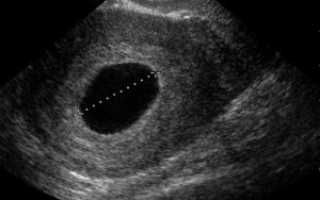

Пустое плодное яйцо или отсутствие эмбриона фото:

Определяется данная патология, на первом УЗИ, на 5-6 неделе беременности. Если нет эмбриона в плодном яйце на мониторе аппарата УЗ-исследования, то врачом выносится диагноз анэмбриония. В некоторых случаях рекомендуется пройти повторное исследование на 7-8 неделе или отследить динамику ХГЧ. Дважды подтвержденный плод без эмбриона является поводом к прерыванию беременности.